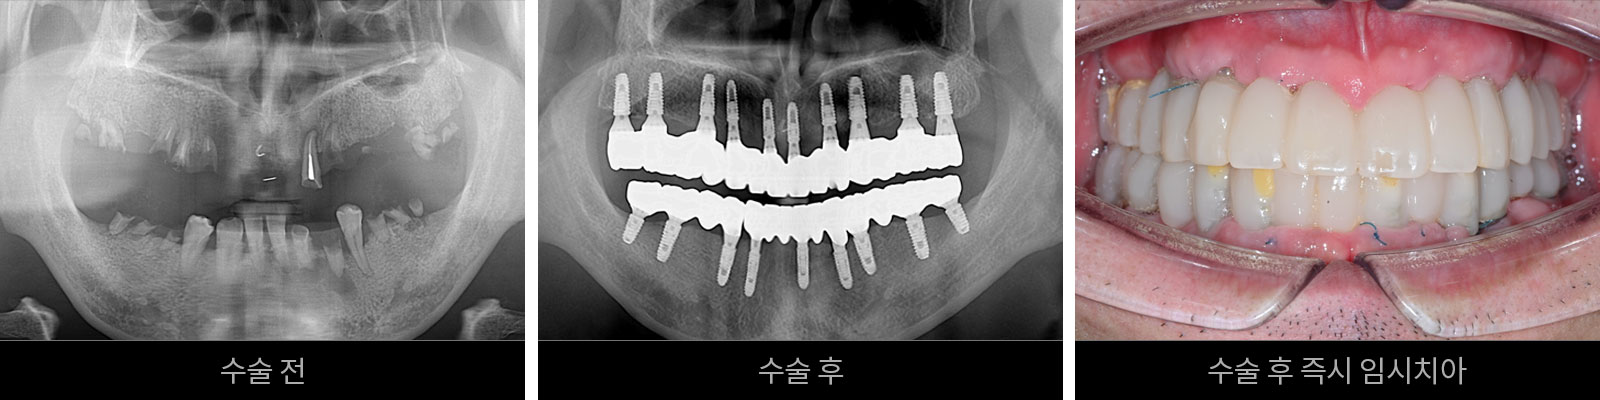

발치 즉시 임플란트

발치 즉시 임플란트 임시치아

발치 후 즉시 임플란트 임시치아의 장점

발치 후 즉시 임플란트는 치료기간을 단축할 수 있을 수 뿐만 아니라 잇몸을 절개할 필요가 없어 마취나 통증에 대한 불안감을 덜 수 있습니다. 또한 발치 후 잇몸뼈가 소실되는 것을 예방해 주는 효과와 함께 잇몸조직이 손상되는 것을 줄여 줄 수 있어 임플란트 시술 후에도 회복이 빠른 장점이 있습니다.